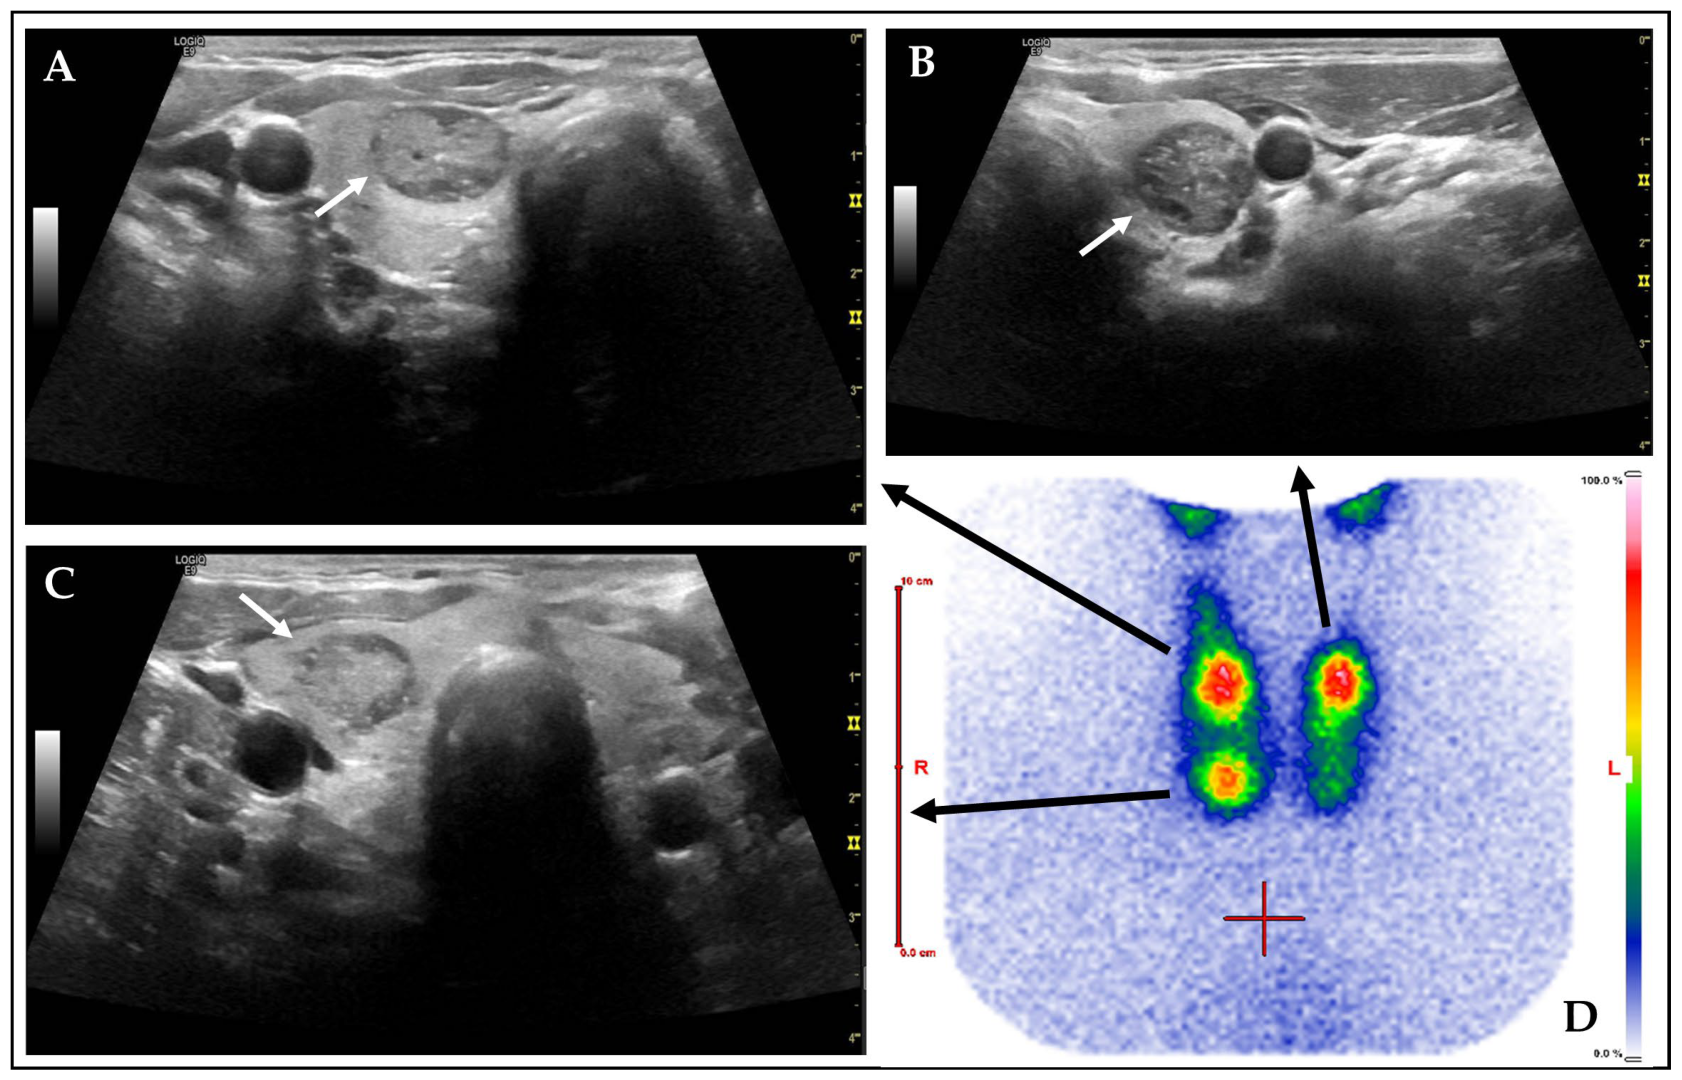

| None | 52 (12.3) | 102 (24.1) | p < 0.001 | rs = 0.603 p < 0.001 |

| Large comet-tail artifacts | 350 (82.5) | 280 (66.0) | p < 0.001 | |

| Macrocalcifications | 145 (34.2) | 109 (25.7) | p = 0.007 | |

| Peripheral (rim) calcifications | 15 (3.5) | 11 (2.6) | p = 0.426 | |

| Punctate echogenic foci | 41 (9.7) | 33 (7.8) | p = 0.330 | |